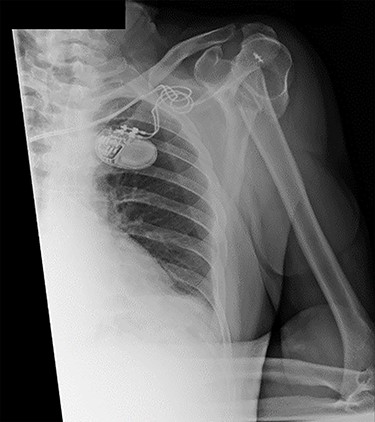

An X-ray of the left shoulder was performed, which revealed acceptable positioning of the fracture. Following a discussion with the patient, a mutual decision was made to manage the injury non-operatively and he was discharged with a collar and cuff sling. Subsequent clinical and radiological review at 1 week and 2 weeks post-injury showed the soft tissues to be healing well and the fracture to be well-positioned (Figs 5 and 6).

Antero-posterior view X-ray taken 1 week post-injury showing acceptable positioning of the fracture.